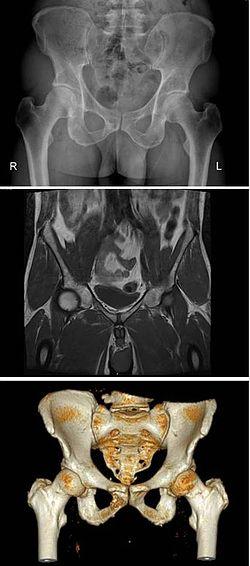

Hip fractures often affect the elderly and occur more often in females, and this is frequently due to osteoporosis. There are also different types of pelvic fracture often resulting from traffic accidents.

There are many anatomical variations of the pelvis. In the female the pelvis can be of a much larger size than normal, known as a giant pelvis or pelvis justo major, or it can be much smaller, known as a reduced pelvis or pelvis justo minor.[42] Other variations include an android pelvis the normal shape of the male pelvis, in women this shape can prove problematic in childbirth.

Nowadays obstetric suitability of the female pelvis is assessed by ultrasound. The dimensions of the head of the fetus and of the birth canal are accurately measured and compared, and the feasibility of labor can be predicted.